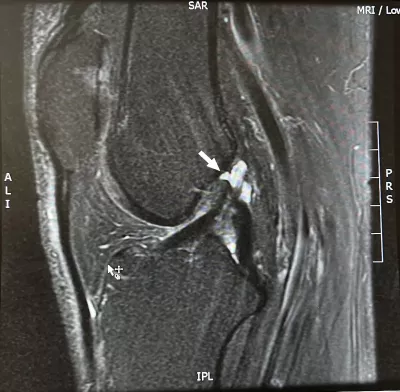

An MRI confirmed what I suspected: I tore my medial collateral ligament (MCL) in my ski accident. But it also showed what I’d hoped it wouldn’t: My anterior cruciate ligament (ACL) was completely ruptured. Not only that, but I had a complex tear of the medial meniscus.

He walks me through the MRI. “These look like chronic injuries, not acute,” he says. “They don’t look how we’d expect them to if they had occurred when you had your ski accident. We’ll never know for sure, but it’s likely that most of what we’re seeing was already there.”

OK, that’s a surprise. I had assumed I already had some ligament damage from a wallyball injury 15 years ago, but I’d thought it was my posterior cruciate ligament (PCL). Oh, and there was that yoga injury where the instructor (notorious for his forceful approach) stood and bounced on my knees to push them to the floor. That, and a bunch of other knee-things in my 62 active years, might explain what we were seeing. And if I’ve been doing OK with those this long, maybe I don’t need surgery now.

What about my torn meniscus? Won’t it need surgery? It’s likely it was also already torn when I had my ski accident. Acute injuries tend to produce simple meniscal tears, but complex tears like mine are usually due to age-related wear and tear (so to speak). And, given what I am able to do (I do brag a little about my recent ski day), he didn’t consider me a candidate for meniscal surgery.